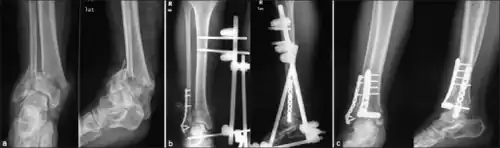

| X-ray of a fracture involving the articular surface of the Tibia | |

A pilon fracture, is a fracture of the distal part of the tibia, involving its articular surface at the ankle joint. Pilon fractures are caused by rotational or axial forces, mostly as a result of falls from a height or motor vehicle accidents. Pilon fractures are rare, comprising 3 to 10 percent of all fractures of the tibia and 1 percent of all lower extremity fractures, but they involve a large part of the weight-bearing surface of the tibia in the ankle joint. Because of this, they may be difficult to fixate and are historically associated with high rates of complications and poor outcome.[1][2][3][4]

The treatment of pilon fractures depends on the extent of the injury. This includes the involvement of other bones such as the fibula and the talus, involvement of soft tissue, and the fracture pattern. Treatment strategies and fixation methods used include internal and external fixation, as well as staged approaches, with the aim of reducing the fracture, reconstructing the involved bones and restoration of articular surface congruence, with minimal insult to soft tissues.[4][7] Appropriate wound management is important to reduce the high rate of infectious complications and secondary wound healing problems associated with open pilon fractures.[8] Vacuum-assisted wound closure therapy and using a staged protocol (awaiting soft-tissue recovery before extensive reconstructive efforts) may play a positive role.[8]